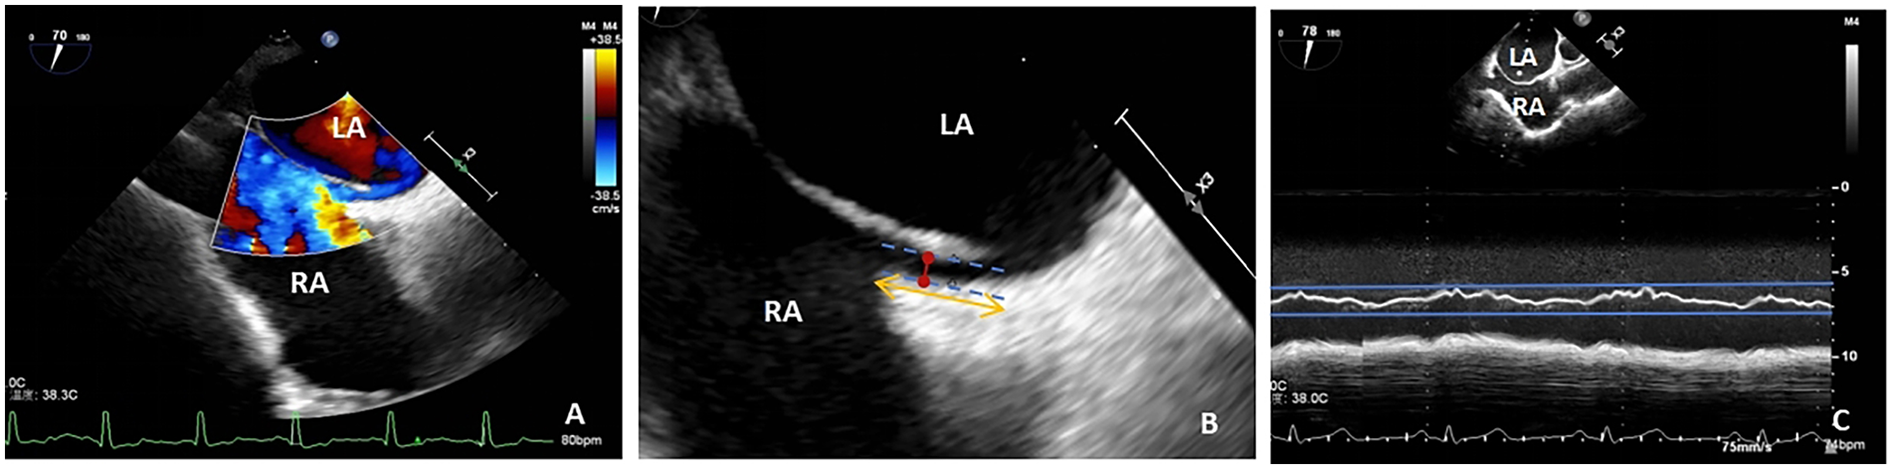

PFO width (maximum distance between primary and secondary septum) and tunnel length (length of overlap between primary and secondary septum) were measured using two-dimensional echocardiography and color Doppler multi-slice multi-angle observations (Figures 2A,B), whereas the amplitude of the atrial septum swing was measured using M-type echocardiography (Figure 2C). ASAs were defined as a septum primum excursion of ≥10 mm from the plane of the atrial septum into the right or left atrium, or swing amplitude ≥15 mm between left and right atria, with a base diameter of ≥15 mm (29). The data were averaged over three measurements taken by an echocardiographer who was blinded to the type of treatment the patient was to receive.

Figure 2

(A) TTE shows a diagonal right-to-left shunt between the left and right atria, diagnosed as patent foramen ovale (PFO); (B) PFO width, maximum distance between the primary and secondary septa (red arrow); PFO tunnel length, length of overlap between the septum primum and the secundum (yellow arrow); (C) atrial septal aneurysm, M-mode measurement of septum primum excursion ≥ 10 mm from the plane of the atrial septum into the right atrium; LA, left atrium; RA, right atrium; TEE, transesophageal echocardiography.